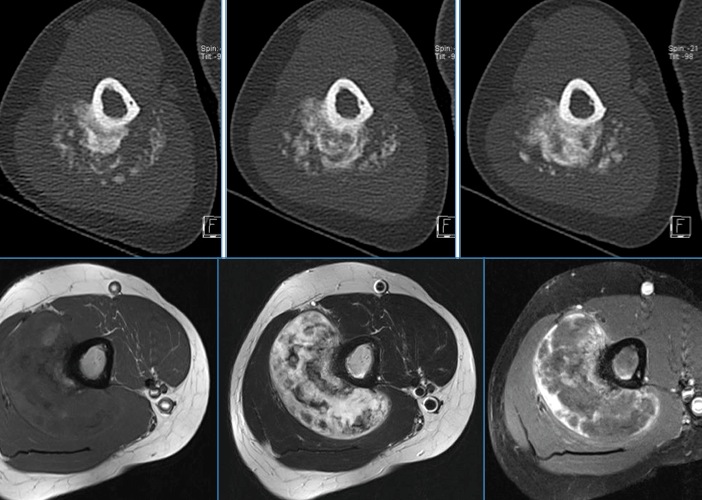

Figure 1 for case Parosteal osteosarcoma ( RID4021 )

Figure 1